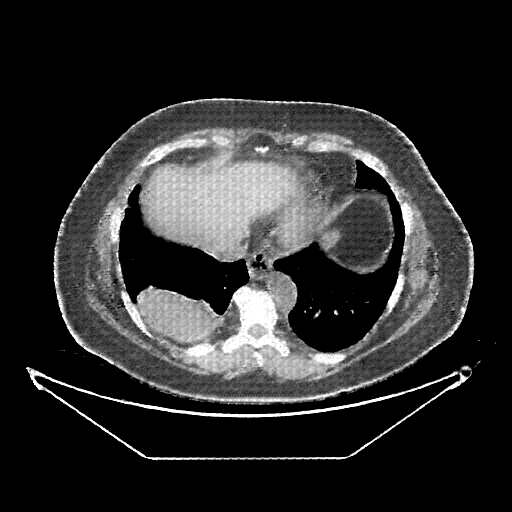

Original VENOUS CT scan

No window - Raw intensity values

Lung window (WL -600, WW 1500 β†’ Low βˆ’1350, High +150)

Mediastinum window (WL 40, WW 400 β†’ Low βˆ’160, High +240)